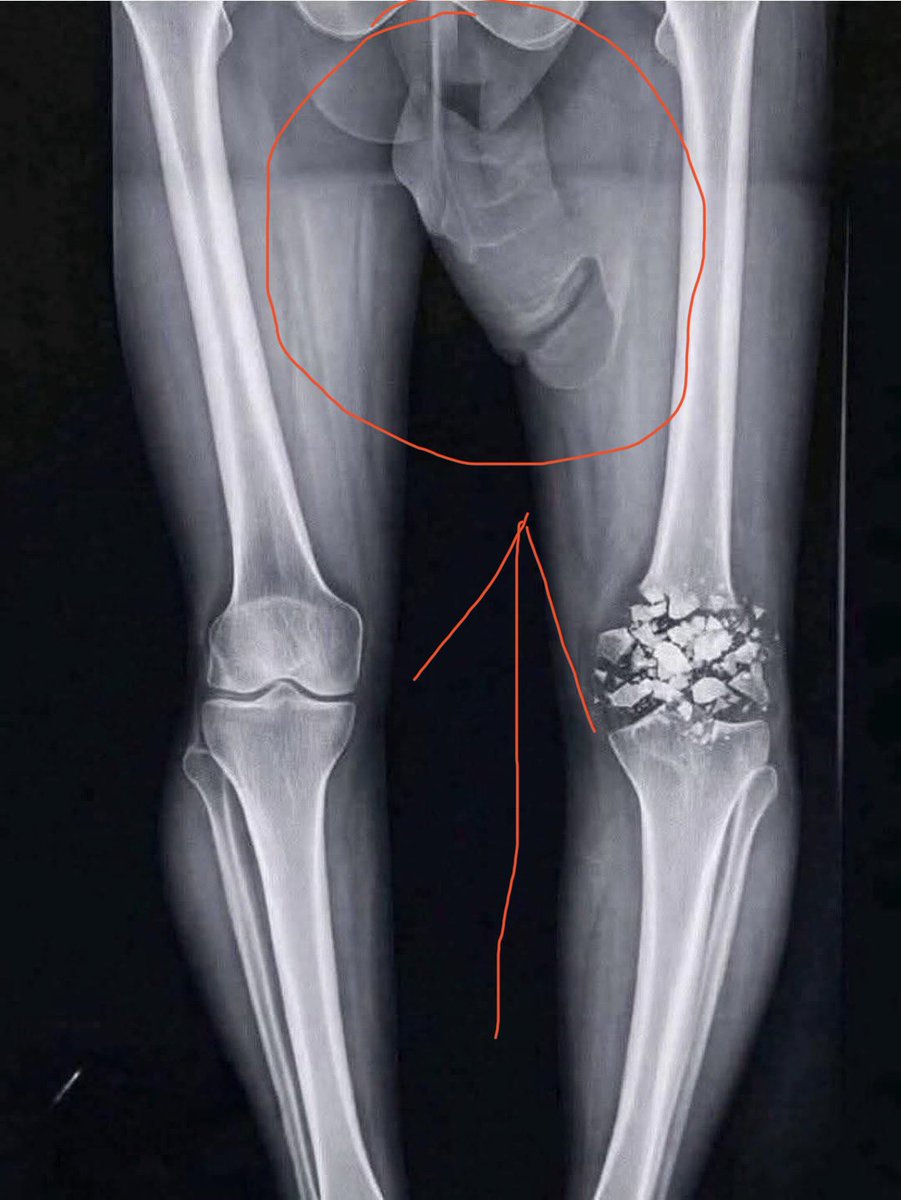

Mbappé ni forzó para un récord ni se borra de partidos importantes. Mbappé lleva tiempo con dolor en la rodilla pero los médicos le decían que todo estaba bien, por lo que el siguió forzando. Ya ha salido a la luz que la resonancia era de la rodilla equivocada. @RMCsport